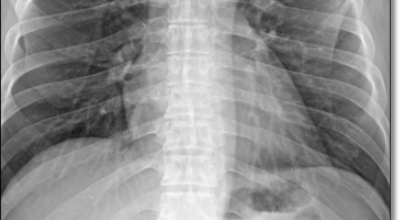

8. 갈비뼈 금간 증상 - 근육통과 금이 간 경우 차이는 거의 없습니다.

일반인이 근육통과 금이 간 경우의 차이는 거의 판별하기 힘들어요. 갈비뼈라고 하는 부분이 눈에 보이도록 붓는 것도 아니고, 멍이 들어서 아픈것도 아니기 때문이지요. 가장 정확하게 판별하는 방법은 엑스레이를 찍는 방법이지요.